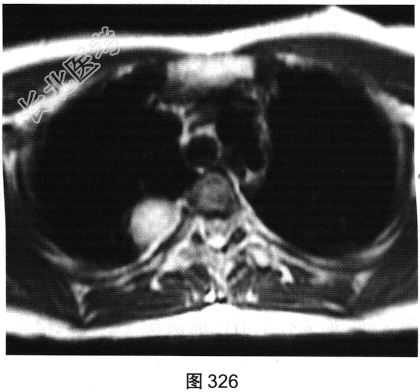

- [材料题] 患者女性,36岁,平素健康,无明显临床症状。单位体检拍摄胸部X线平片提示“右上肺阴影”。遂到大型医院进一步行胸部影像学检查,如图325~图327所示。

B、上述增强扫描包括横轴位和冠状面图像

C、上述冠状面图像为后处理重建图像

G、冠状面示病灶可能来源于椎管内

- 多项选择题3.依据本病例临床和影像学表现,最可能的诊断为( )

D、右后纵隔神经源肿瘤